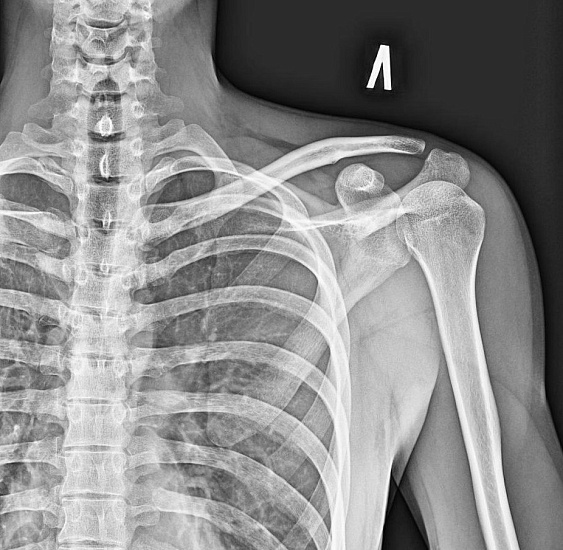

Рентгенография лопатки – важный метод прицельного исследования, который позволяет оценить состояние лопатки.

Диагностическая услуга выполняется в двух проекциях.

Рентген позволяет оценить наличие костно-травматической патологии лопатки.